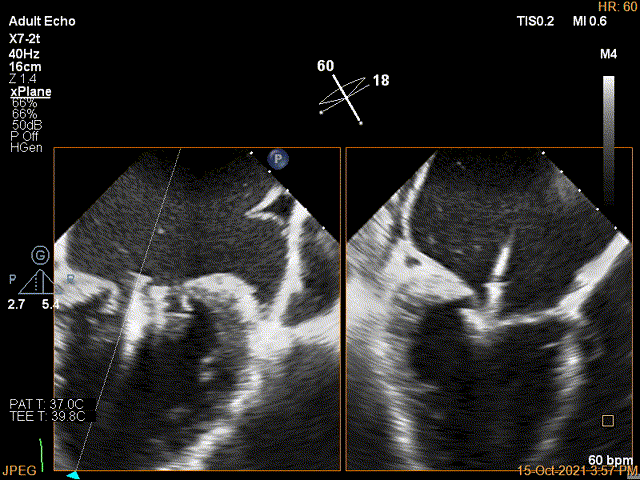

2D视图下trajactiory

X-plane:下夹子尝试先捕获1区脱垂瓣叶

3D证实夹子内侧残余Flail

2D视图下进第二个夹子并建立trajectory

将第二个夹子置于第一个夹子侧并内调节Rotate